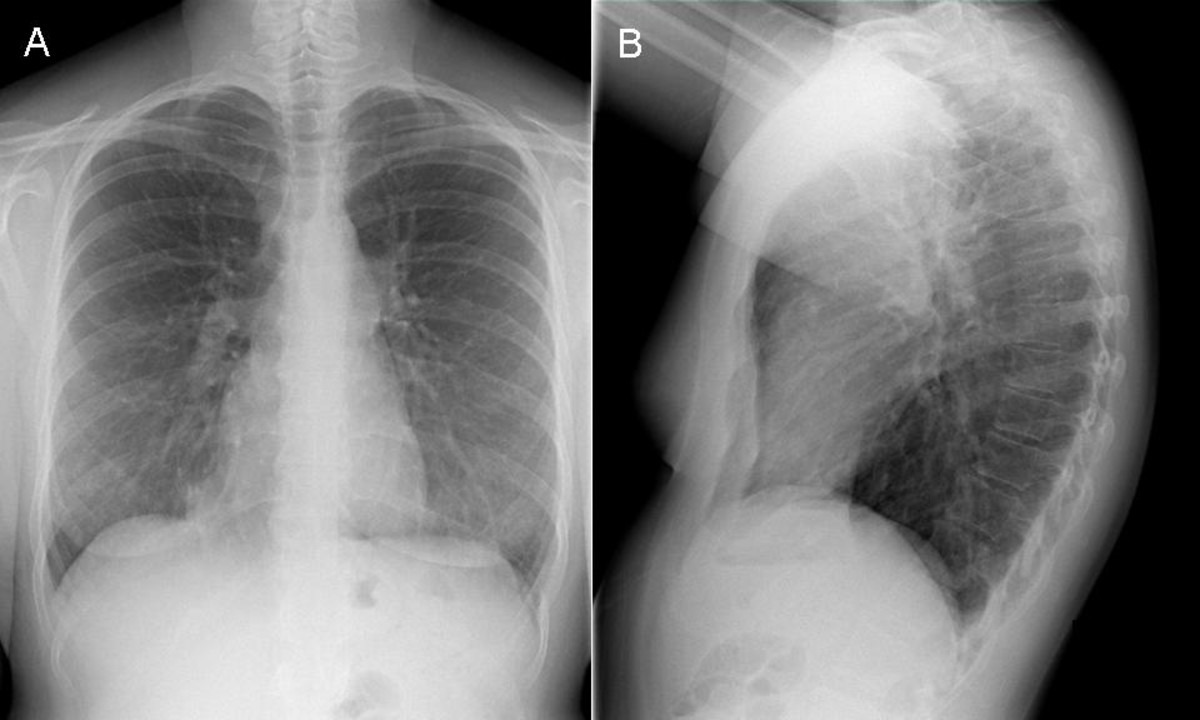

Normal Chest Radiography and Computed Tomography Radiology Key